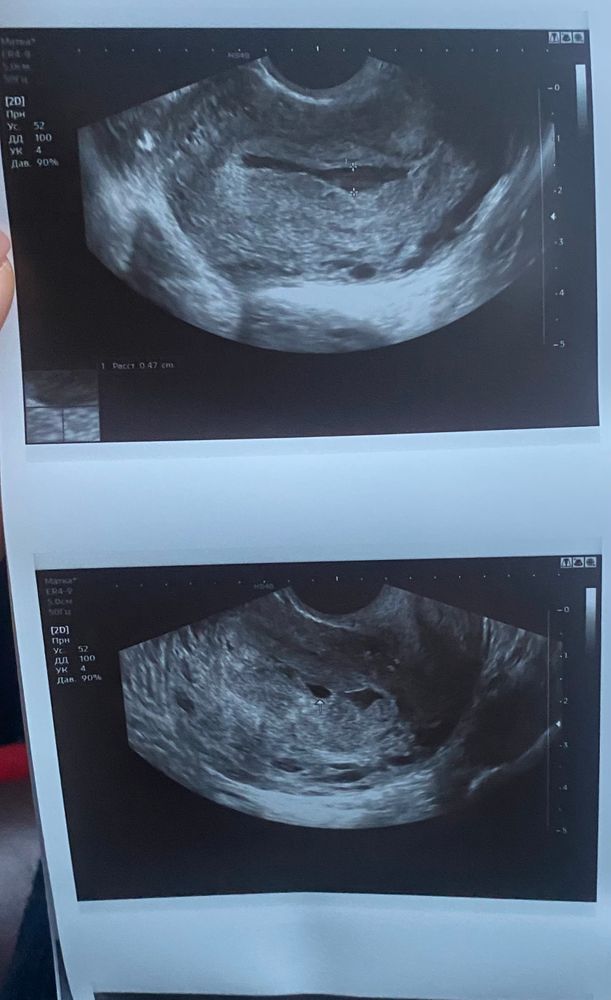

Плодное яйцо неправильной формы, полость матки расширена

Полина Викторовна , да, я очень рано пошла в первый раз не узи.. не нужно было. Сделала это чтобы исключить внематочную, а возникло еще больше вопросов. Вот прикрепила фото..

Изображение Изображение Изображение